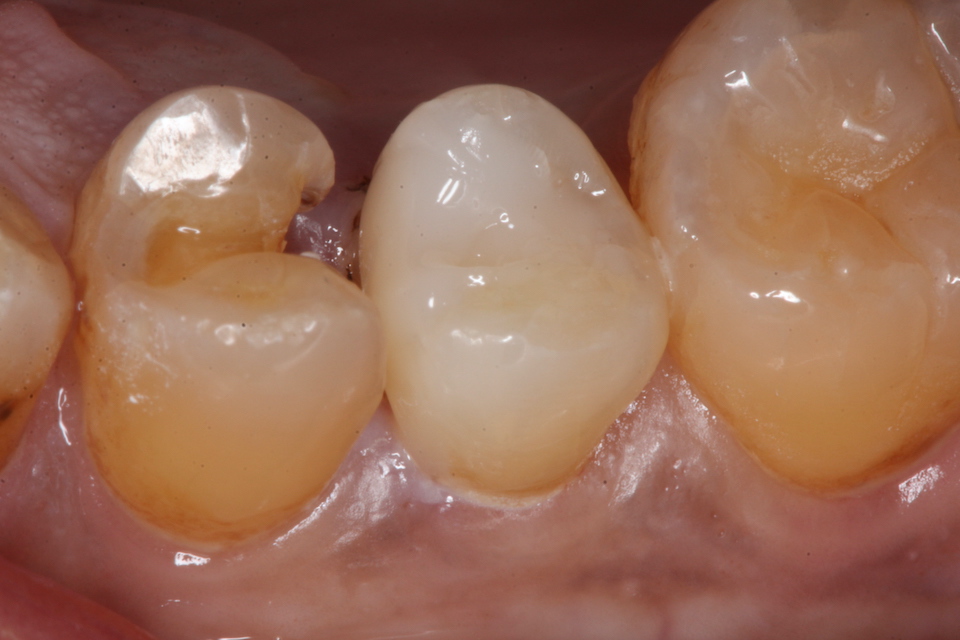

下顎7番の頬側歯茎部カリエスの原因 2025.06.04